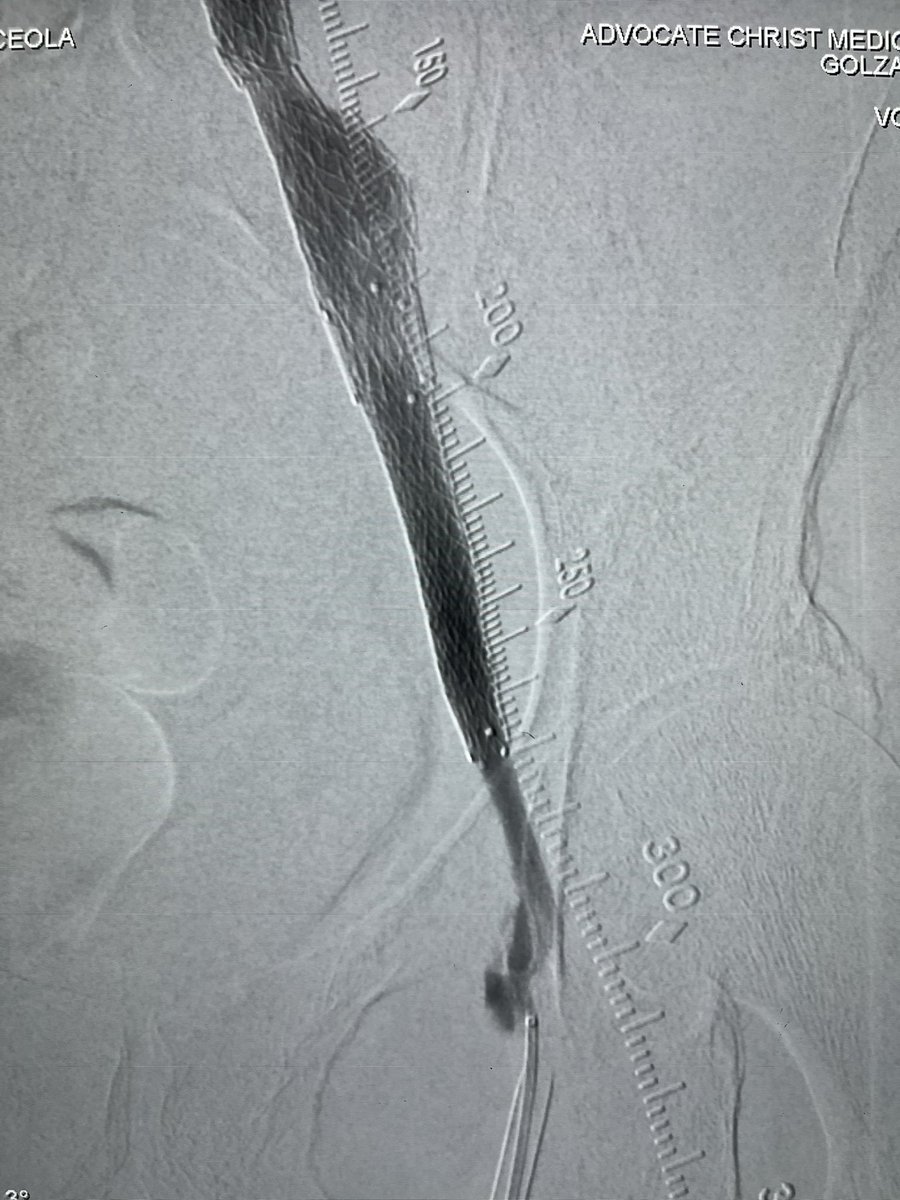

We completed the first 2 perc bypass in Illinois w #Detour @endologix Excited for this groundbreaking technology to be in the hands of #limbsalvage docs around the globe. @ShawnPenn33 @DeanFerreraDO @Abd_Alrifai @MarcoShaker @tlevin @advocatehealth

3

4

13